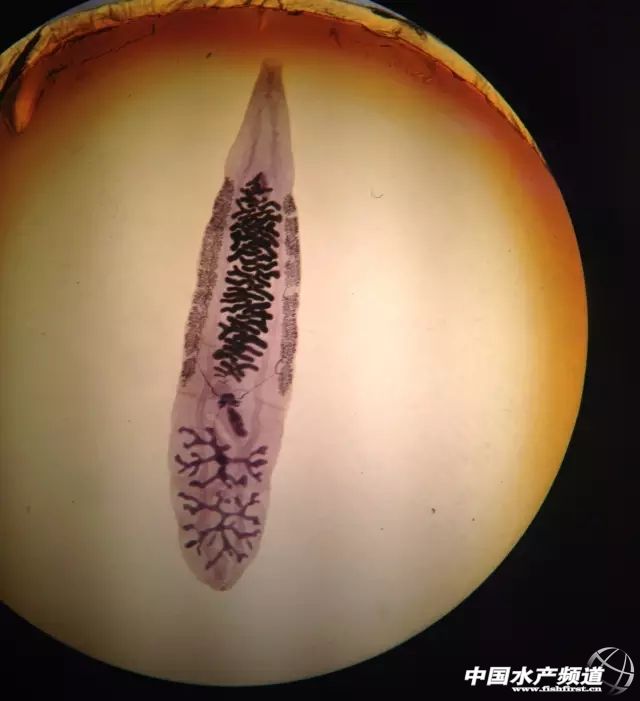

| 中國水產(chǎn)頻道綜合報(bào)道, 纖毛蟲 纖毛蟲屬纖毛門(Ciliophora),大多數(shù)纖毛蟲在生活史的各個(gè)階段都有纖毛,以纖毛作為運(yùn)動(dòng)細(xì)胞器。纖毛在蟲體表面有節(jié)律地順序擺動(dòng),形成波狀運(yùn)動(dòng),加之纖毛在排列上稍有傾斜,因而推動(dòng)蟲體以螺旋形旋轉(zhuǎn)的方式向前運(yùn)動(dòng)。蟲體也可依靠纖毛逆向擺動(dòng)而改變運(yùn)動(dòng)方向,向后移動(dòng)等。在蟲體的近前端有一明顯的胞口,下接胞咽,后端有一個(gè)較小的胞肛。多數(shù)纖毛蟲營自生生活,少數(shù)可寄生于無脊椎動(dòng)物和脊椎動(dòng)物的消化道內(nèi)。 車輪蟲 車輪蟲寄生在多種淡水動(dòng)物的鰓及皮膚上,主要危害苗種,嚴(yán)重感染時(shí)可引起苗種大批死亡。車輪蟲用附著盤附著在魚體的鰓絲或皮膚上,并來回滑動(dòng)。游泳時(shí)一般用反口面向前像車輪一樣轉(zhuǎn)動(dòng),所以稱為車輪蟲。生殖用縱二分裂法和接合生殖。 車輪蟲蟲體側(cè)面觀如氈帽狀,反面觀圓碟形,運(yùn)動(dòng)是如車輪轉(zhuǎn)動(dòng)樣。隆起的一面為前面或稱口面,相對而凹入的一面為反口面?诿嫔嫌邢蜃蠡蚍磿r(shí)針發(fā)方向螺旋狀環(huán)繞的口溝,其末端通向胞口?跍蟽蓚(cè)個(gè)生一行纖毛,形成口帶,直達(dá)前庭腔。反口面的中間為齒環(huán)和輻線環(huán)。在輻線環(huán)上方有一馬蹄形的大核,一個(gè)長形的小核和一個(gè)伸縮泡,其中部想體內(nèi)凹入,形成附著盤,用于吸附在宿主身上。車輪蟲用附著盤附著在魚體的鰓絲或皮膚上,并來回滑動(dòng)。游泳時(shí)一般用反口面向前像車輪一樣轉(zhuǎn)動(dòng),所以稱為車輪蟲。生殖用縱二分裂法和接合生殖。 魚鲺 魚鲺身體橢圓形,透明。蟲體分頭、胸、腹三部分。頭部的腹面有一對用作吸附在魚體上的吸盤和一個(gè)刺破魚皮膚的口刺。胸部分四節(jié),每節(jié)有一對游泳足。腹部不分節(jié),為橢圓形的葉片,是魚虱的呼吸器官。魚虱沒有卵囊,卵直接產(chǎn)在水生植物或石塊上。卵圓形,黃色或褐色,外面有一層膠質(zhì)物,借以固定在其體物體上。水溫29-31℃時(shí),10-14天即可孵出幼蟲。幼蟲孵出后,若兩天內(nèi)找不到寄主,即行死亡。魚虱離開魚體后,可在水中自由生活較短時(shí)間,所以它可以自行由一尾魚轉(zhuǎn)移到另一尾魚體上去,也能隨水流入其他水體中。 小瓜蟲 小瓜蟲為凹口科、小瓜蟲屬、多子小瓜蟲。這是一類體型比較大的纖毛蟲。它的形態(tài)在幼蟲期和成蟲期有很大的差別。小瓜蟲的幼蟲侵襲魚的皮膚和鰓,尤以皮膚為普遍。當(dāng)幼蟲感染了寄主后,就鉆進(jìn)皮膚或鰓的上皮組織,把身體包在由寄主分泌的小囊胞內(nèi),在胞內(nèi)生長發(fā)育,變?yōu)槌上x。成蟲沖破囊胞落入水中,自由游動(dòng)一段時(shí)間后落在水體底部,靜止下來,分泌一層膠質(zhì)的胞囊。胞囊里的蟲體分裂法繁殖,產(chǎn)生幾百甚至成千的纖毛幼蟲。幼蟲出來,在水中自由游動(dòng),尋找寄主,這就是小瓜蟲的感染期。幼蟲感染了新寄主,又開始它的生活史。 錨頭蚤 錨頭蚤(俗稱錨頭蟲)屬節(jié)肢動(dòng)物甲殼類的一種。只有雌蟲才寄生在魚體上,長約1厘米。蟲體的后端,帶有1對卵囊。頭部分有叉狀兩角,似船錨,故此而得名。蟲體寄生四周組織常紅腫發(fā)炎,同時(shí)靠近傷口的鱗片被錨頭蚤的分泌物溶解,腐蝕成缺口。魚體初被蟲體侵入時(shí),表現(xiàn)不安,食欲不好,繼而身體瘦弱,游動(dòng)緩慢。 此蟲可侵入鯉魚、鰱魚、鳙魚、草魚等魚的體表,對幼魚危害特別嚴(yán)重,可引起死亡(對大魚主要是影響生長)。此病流行地區(qū)廣,全國各養(yǎng)魚地區(qū)都有發(fā)現(xiàn),終年可見,夏、秋季能引起嚴(yán)重流行病。 三代蟲 三代蟲,學(xué)名Gyrodactylus。三代蟲是雌雄同體,有卵巢2個(gè)及精巢一個(gè),位于身體后部。三代蟲為卵胎生,在卵巢的前方有未分裂的受精卵及發(fā)育的胚胎,在大胚胎內(nèi)又有小胚胎,因此稱為三代蟲。三代蟲身體扁平縱長,前端有兩個(gè)突起的頭器,能夠主動(dòng)伸縮,又有單細(xì)胞腺的頭腺一對,開口于頭器的前端,此蟲沒有眼點(diǎn),口位于頭器下方中央,下通咽、食道和兩條盲管狀的腸在體2兩側(cè)。體后端的固著器為一大形的固著盤。盤中央有2個(gè)大錨,大錨之間由2條橫捧相連,盤的邊緣有16個(gè)小鉤,有秩序地排列著。三代蟲用后固著器上的大錨和小鉤固著在寄主的身上,同時(shí)前端的頭腺也分泌粘液,用以粘著在寄主體上或像尺蠖一樣的慢慢爬行。 指環(huán)蟲 指環(huán)蟲的蟲體通常為長圓形,動(dòng)作像尺蠖,寄生在各種魚類的鰓上、身體前端有4個(gè)瓣?duì)畹念^器常常伸縮,頭部背面有4個(gè)眼點(diǎn),在體后端腹面有一個(gè)圓形的固著盤,盤的中央有2個(gè)大錨,盤的邊緣有14個(gè)小構(gòu),在兩大鉤之間有l(wèi)-2條橫棒相連?谕ǔ3使軤,可以伸縮,位于身體前端腹面靠近眼點(diǎn)附近,口下接一圓形的咽,咽下為食管,接著是分2支的腸,2條腸的末端通常在后固著盤的前面相連,使整個(gè)腸成環(huán)狀,但也有不相連而呈直管狀的。 九江頭槽絳蟲 九江頭槽絳蟲蟲體扁平,帶狀,乳白色,長20-230毫米。頭節(jié)心臟形,頂端有一明顯的頂盤,兩側(cè)各自有一個(gè)深的吸溝。頸節(jié)不明顯。頸節(jié)之后由許多片組成,前端節(jié)片寬大于長,成熟片近方形,孕卵節(jié)片長稍大于寬。每個(gè)節(jié)片內(nèi)有一套雌雄性生殖器官。 華枝睪吸蟲 華枝睪吸蟲Clonorchis sinensis (Cobbold, 1875) Looss, 1907,簡稱華支睪吸蟲,又稱肝吸蟲(liver fluke),華肝蛭。成蟲寄生于人體的肝膽管內(nèi),可引起華支睪吸蟲病(Clonorchiasis ),又稱肝吸蟲病。本蟲于1874年首次在加爾各答一華僑的膽管內(nèi)發(fā)現(xiàn),1908年才在我國證實(shí)該病存在。1975年在我國湖北江陵西漢古尸糞便中發(fā)現(xiàn)本蟲蟲卵,繼之又在該縣戰(zhàn)國楚墓古尸見該蟲卵,從而證明華支睪吸蟲病在我國至少已有2300年以上歷史。華支睪吸蟲體形狹長,背腹扁平, 前端稍窄,后端鈍圓,狀似葵花子,體表無棘。蟲體大小一般為10~25×3~5mm。 碘孢子蟲 碘泡蟲屬(Myxobolus)是原生動(dòng)物門、粘體動(dòng)物亞門、粘孢子蟲綱、雙殼目、碘泡蟲科的一屬。孢子卵形或橢圓形,扁平,前端有2個(gè)極囊,等大或不等。孢中質(zhì)中有1個(gè)嗜碘泡。 有些種類可造成嚴(yán)重的魚病,如草魚餅形碘泡蟲(M. artus)、鳙鰓上的異型碘泡蟲(M. dispar)、鰱碘泡蟲(M. drjagini)等。它們廣泛寄生于魚類,所有飼養(yǎng)魚類和常見野雜魚均可被寄生。寄生部位有:鰓、皮膚、鰭、腦、膽、脾、腎、肌肉、膀胱、鰾。其他器官如輸尿管、鼻腔、生殖腺亦照樣可受侵襲。不論是江湖的魚類或小溪、小河、池塘,小溝、小蕩的魚類均可檢出。碘泡蟲感染率(粘孢子蟲類的其他屬亦有)有明顯的季節(jié)變化,其感染亦與宿主個(gè)體的大小有一定的關(guān)系,但與性別的關(guān)系不大。 斜管蟲 斜管蟲蟲體有背腹之分,背部稍隆起。腹面觀左邊較直,右邊稍彎,左面有9條纖毛線,右面有7條,每條纖毛線上長著一律的纖毛。腹面中部有一條喇叭狀口管。大核近圓形,小核球形,身體左右兩邊各有一個(gè)伸縮泡,一前一后。寄生在魚的鰓、體表,刺激寄主分泌大量粘液,使寄主皮膚表面形成蒼白色或淡藍(lán)色的粘液層,組織被破壞,影響魚的呼吸功能。病魚食欲差,魚體消瘦發(fā)黑,靠近塘邊浮在水面作側(cè)臥狀,不久即死亡。此病流行廣泛,對魚苗、魚種危害較大,能引起大量死亡,該寄生蟲繁殖最適溫度為12~18℃,初冬和春季最為流行。 刺激隱核蟲 刺激隱核蟲(Cryptocaryon irritans Brown) 又叫海水小瓜蟲,屬原生動(dòng)物門、纖毛亞門、寡膜纖毛綱、膜口亞綱、膜口目、凹口科、隱核蟲屬的一種。刺激隱核蟲常寄生于海水硬骨魚類的皮膚、鰓的上皮下,可引起魚類的傳染性疾病。刺激隱核蟲與寄生淡水魚類的多子小瓜蟲(Ichthyophthirius multifiliis)很相似,所以又稱咸水小瓜蟲。刺激隱核蟲呈球形或卵形,全身被有纖毛,前端有一胞口。區(qū)別在于,其大核呈卵圓形團(tuán)狀,4~8個(gè),一般4個(gè),相連呈念珠狀,作"U"形排列。蟲體透明度低,顯微鏡下常呈黑乳白色,難見其大核。 |